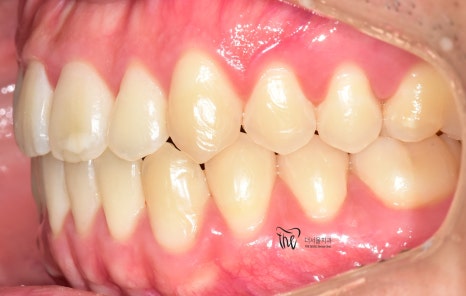

『덧니교정 치료 사례, 인비절라인 장치 사용』

정면 및 측면에서 봤을 때, 측절치의 후방위치에

따라서 반대교합 형태를 보여주고 있으면서

이 때문에 송곳니가 더 덧니처럼 보여지는 느낌을

받고 있는 모습을 볼 수 있습니다.

나아가, 하악의 전치부 쪽에도 총생 현상이

같이 관찰이 되면서 이런 비심미적인 요소들을

개선시키고 싶은 마음으로 더서울치과에

내원하셨던 분입니다.

치열이 많이 가지런하게 펴진 것을 볼 수 있고,